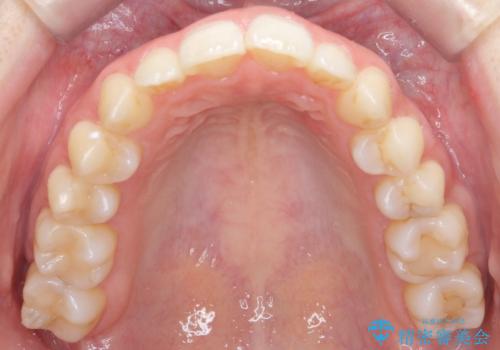

歯の着色を落としたい

- 表面の着色を気にされて、ご来院されました。

お話しをしたところ、リーズナブルに短時間で綺麗にしたいとの事でした。

そこでPMTCの30分コースで、目立つ部分を中心に落としていきました。